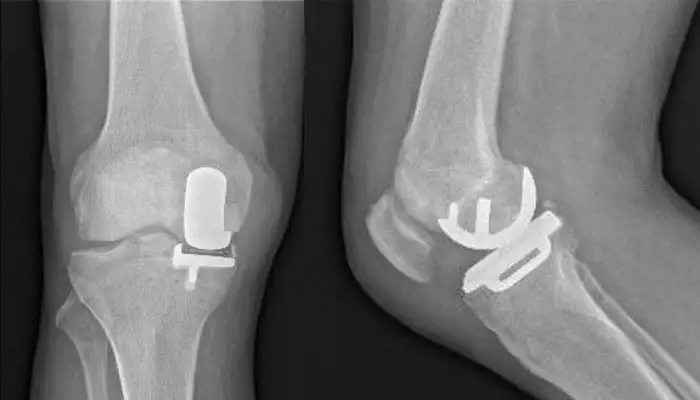

Prótesis total o parcial de rodilla (artroplastia). Consiste en la sustitución parcial o total de las superficies articulares desgastadas para restablecer la función de la rodilla.